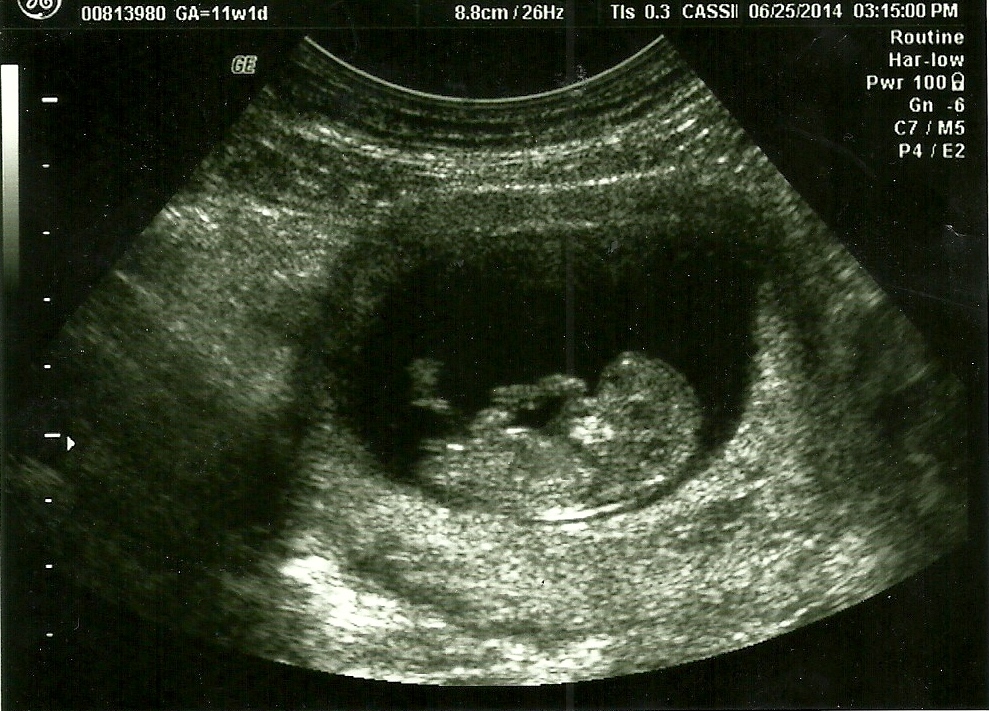

Here is the 11w1d scan. The others are 13w2d